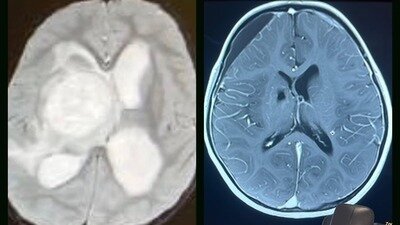

Picture ONE: My daughter's brain imaging at diagnosis on the left and after two years on full extract cannabis oil, her tumor free scan on the right. All blood work and imaging fully medically documented.